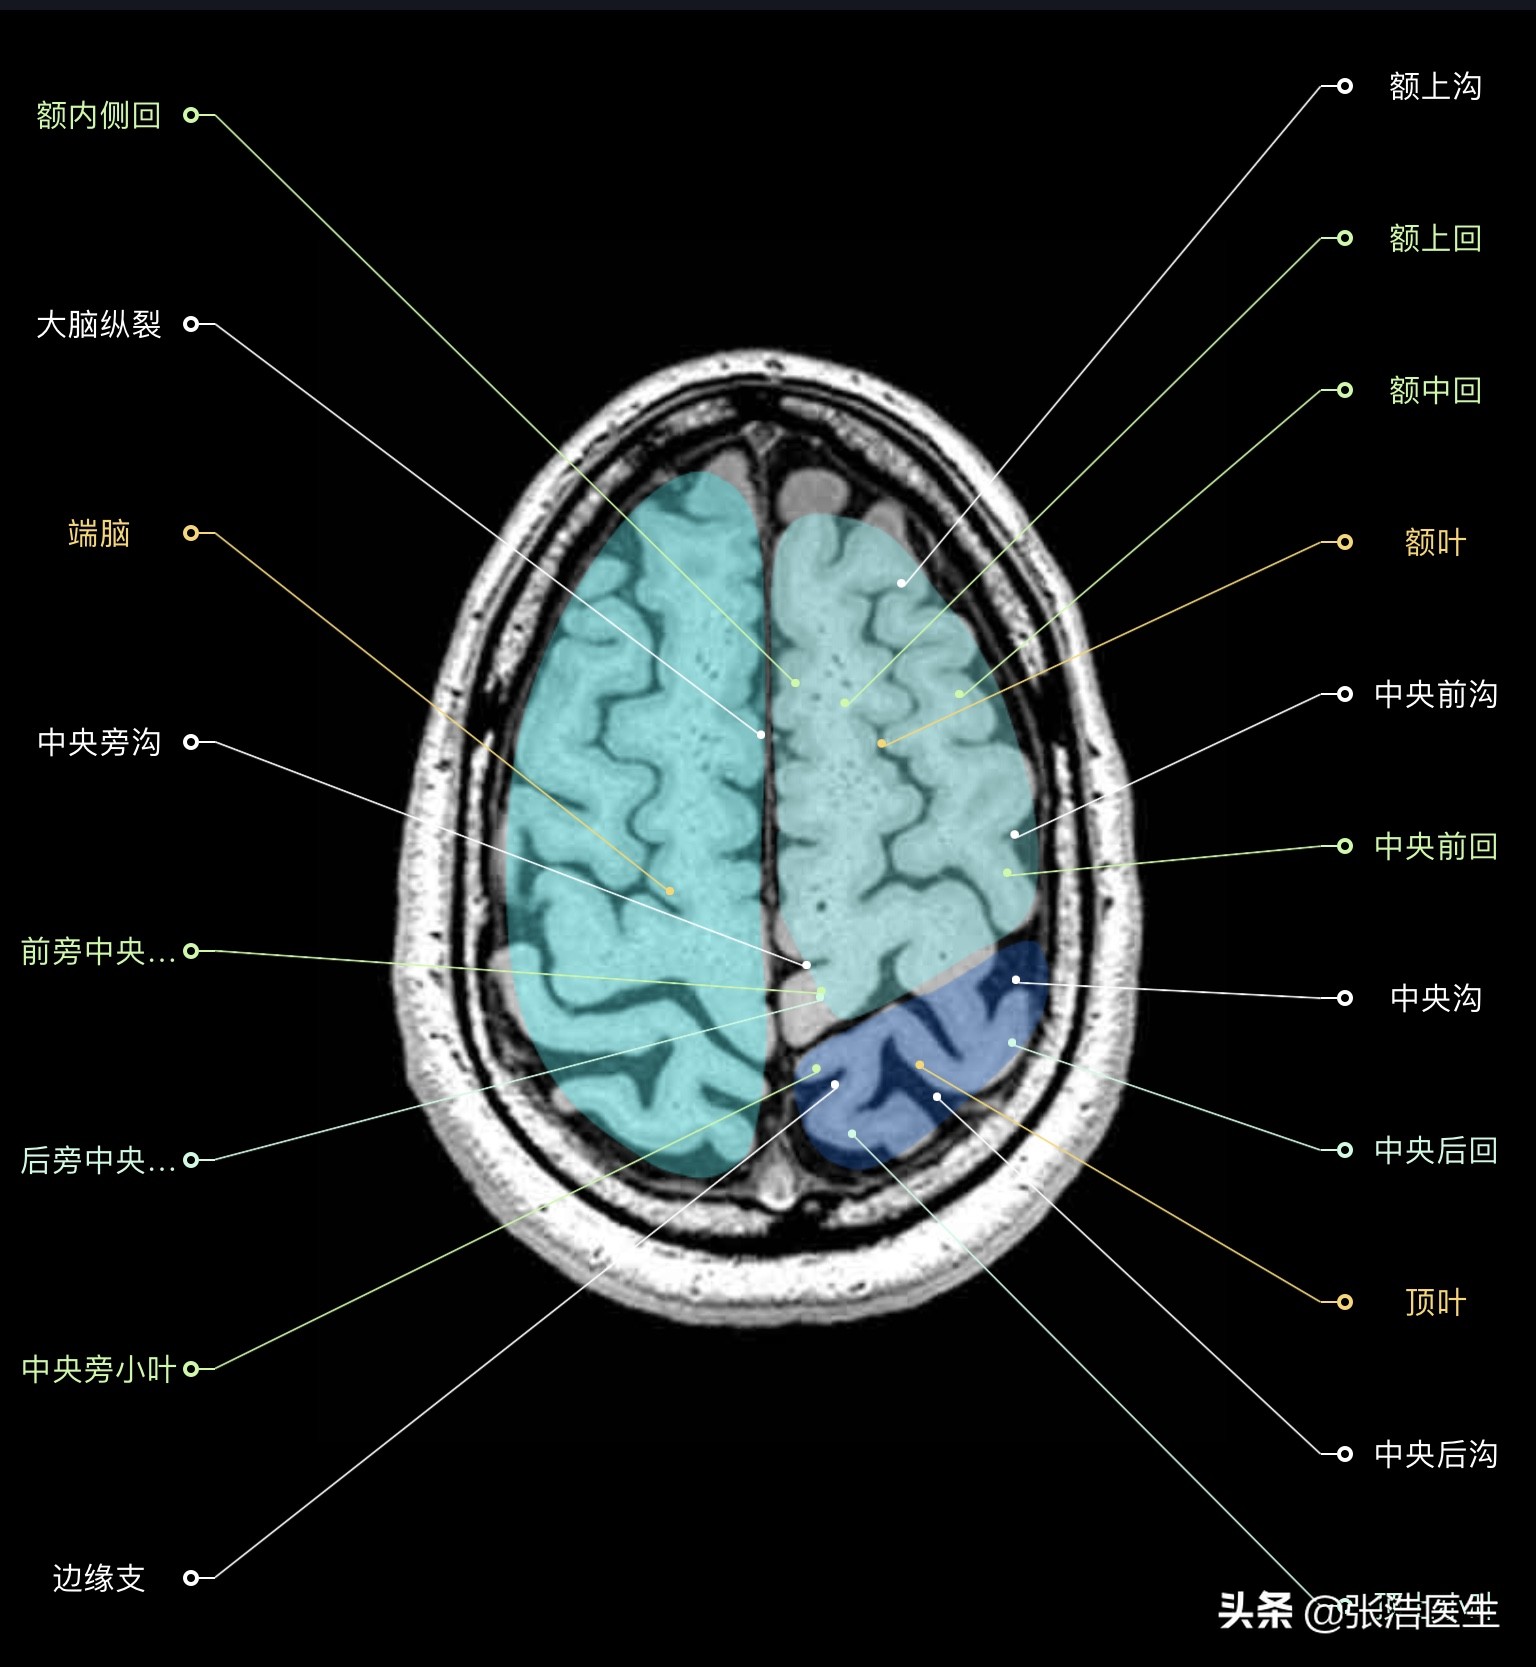

颅脑MRI横断面高清解剖图谱(图层1)